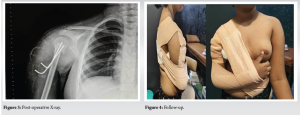

Under general anesthesia, closed reduction was achieved using the Kapandji and Jyoctiky maneuver, and the fracture was stabilized with percutaneous K-wires under fluoroscopic guidance (Fig. 2). Post-reduction alignment was satisfactory, with complete varus correction and mild residual translation (Fig. 3). The patient’s arm was immobilized with Dynaplast strapping (Fig. 4).